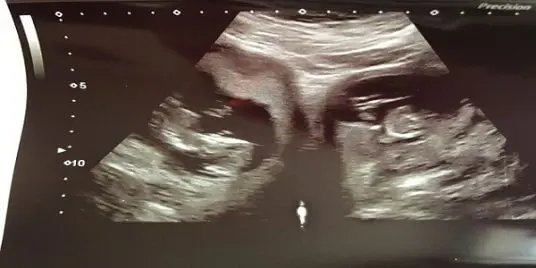

يُعد الحمل بتوأم أمرًا شائعًا وعاديًا، ولكن بالنسبة لجينيفر آشوود، فقد تسبب حملها بصدمة وحيرة كبيرة للأطباء؛ حين اكتشفوا أنها تمتلك رحمين، وحملت في كليهما بنفس الوقت.

وتعد تلك الحالة نادرة للغاية، فهي تحدث لواحدة من بين 500 مليون سيدة، وليس هناك سوى 100 حالة مسجلة على مستوى العالم.

وكشفت صحيفة "ديلي ميل" البريطانية، أن حالة جينيفر آشوود (31 عامًا)، تُعرف باسم "رحم ثنائي القرن"، حيث يحتوي بطن الأم على رحمين منفصلين.

وعلى الرغم من إنجابها سابقًا طفلتها ميلي البالغة من العمر الآن 8 أعوام، إلا أنها لم تعلم بحالتها النادرة، ولم تكتشف امتلاكها لرحمين سوى أثناء الفحص بالسونار، في الأسبوع الـ 20 من حملها الأخير.